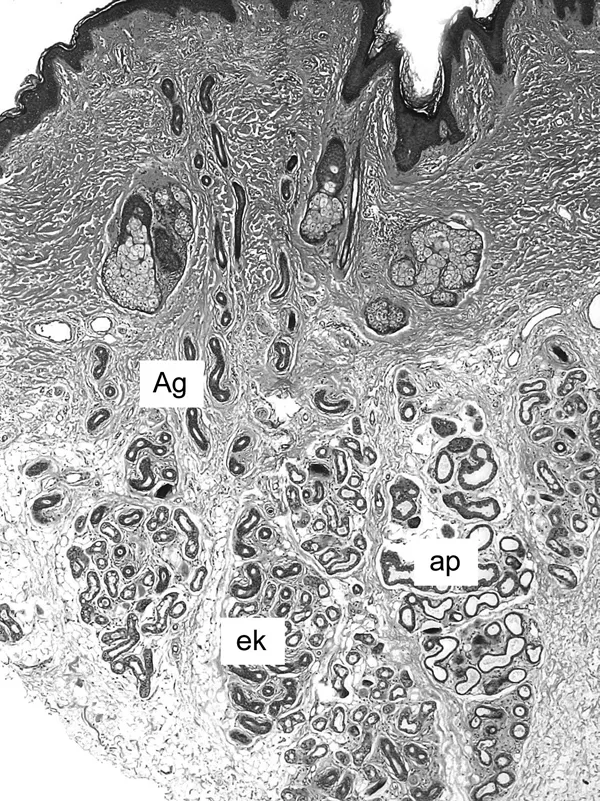

Bis heute hat sich beim Menschen eine Unterteilung der Schweißdrüsen in zwei verschiedene Typen durchgesetzt: die ekkrinen und die apokrinen Schweißdrüsen (Abb. 2).

Abbildung 2: Histologische Ansicht der menschlichen Haut. Die Hautprobe stammt aus dem Bereich der Achselhöhle. Es zeigen sich die Hautanhangsgebilde wie Talg- und Schweißdrüsen. Deutlich ist der Unterschied zwischen den kleineren ekkrinen (ek) und größeren apokrinen (ap) Schweißdrüsen zu erkennen. Ein Ausführungsgang (Ag) der ekkrinen Drüse zur Hautoberfläche ist angeschnitten.

Bei den ekkrinen Schweißdrüsen gibt es zwei Anteile. Zum einen das sekretorische Drüsenendstück, in welchem die Produktion des Schweißes erfolgt. Dieser Teil ist sozusagen die Fabrik, in welcher der Schweiß hergestellt wird. Daran schließt sich in Richtung der Hautoberfläche ein Ausführungsgang (wie ein »Abflussrohr«) an, der für die Ausleitung des Schweißes an die Hautoberfläche verantwortlich ist (Abb. 2). Die ekkrinen Schweißdrüsen befinden sich in den tieferen Anteilen der Led...